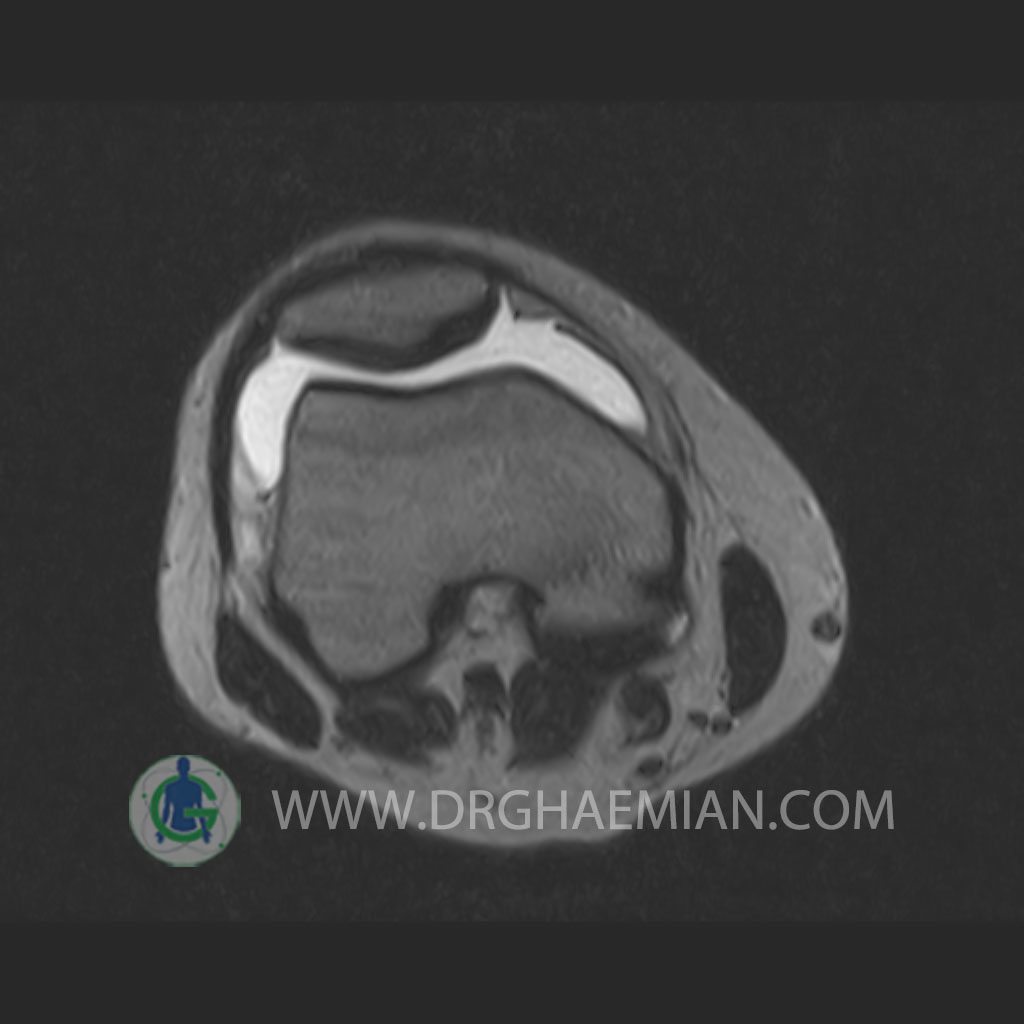

RIGHT KNEE MRI

(Without contrast)

Technique: Sagittal T1, T2 , Axial GE , coronal & sagital fatsat .

– Knee joint effusion with soft tissue swelling around the knee

– Grade 2 signal change in P.H. of medial meniscus with partial tearing of posterior root & meniscal extrusion

– Grade 2 signal change in P.H. of lateral meniscus with meniscal extrusion

– Complete tearing of ACL ( femoral detachment ) with bone bruise in plateau of tibia

are seen